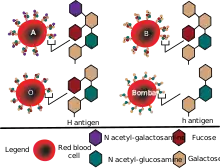

Individuals with the rare Bombay phenotype (hh) do not express H antigen (also called substance H), the antigen which is present in blood group O. As a result, they cannot make A antigen (also called substance A) or B antigen (substance B) on their red blood cells, whatever alleles they may have of the A and B blood-group genes, because A antigen and B antigen are made from H antigen. For this reason people who have Bombay phenotype can donate red blood cells to any member of the ABO blood group system (unless some other blood factor gene, such as Rh, is incompatible), but they cannot receive blood from any member of the ABO blood group system (which always contains one or more of A, B or H antigens), but only from other people who have Bombay phenotype.[1]

Biosynthesis of the H, A and B antigens involves a series of enzymes (glycosyl transferases) that transfer monosaccharides. The resulting antigens are oligosaccharide chains, which are attached to lipids and proteins that are anchored in the red blood cell membrane. The function of the H antigen, apart from being an intermediate substrate in the synthesis of ABO blood group antigens, is not known, although it may be involved in cell adhesion. People who lack the H antigen do not suffer from deleterious effects, and being H-deficient is only an issue if they need a blood transfusion, because they would need blood without the H antigen present on red blood cells.

The specificity of the H antigen is determined by the sequence of oligosaccharides. More specifically, the minimum requirement for H antigenicity is the terminal disaccharide fucose-galactose, where the fucose has an alpha(1-2)linkage. This antigen is produced by a specific fucosyl transferase (Galactoside 2-alpha-L-fucosyltransferase 2) that catalyzes the final step in the synthesis of the molecule. Depending upon a person's ABO blood type, the H antigen is converted into either the A antigen, B antigen, or both. If a person has group O blood, the H antigen remains unmodified. Therefore, the H antigen is present more in blood type O and less in blood type AB.